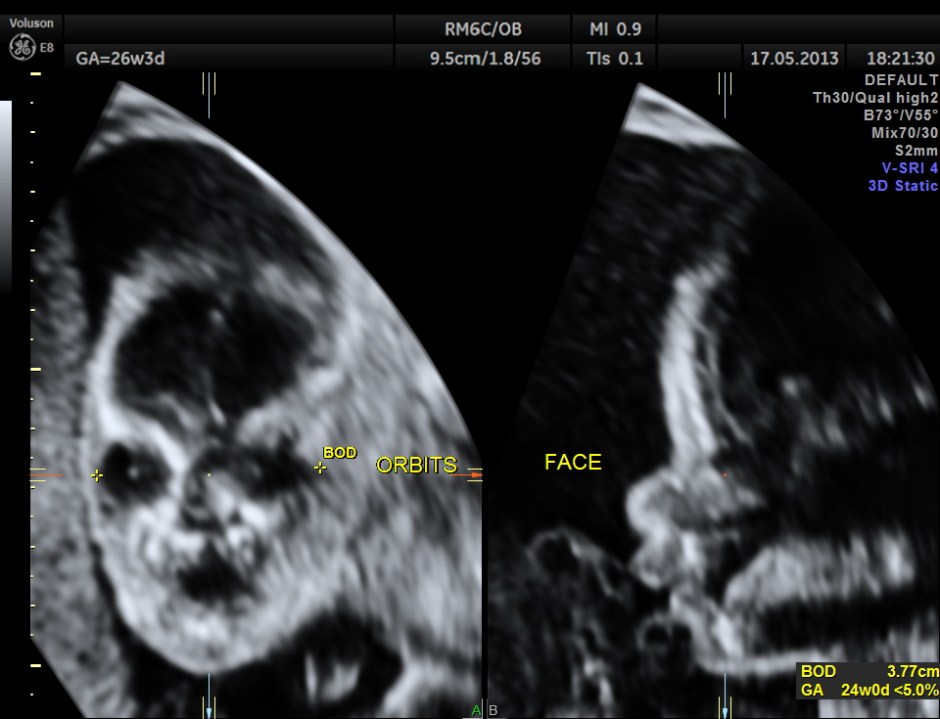

The following images show the face and the palate.